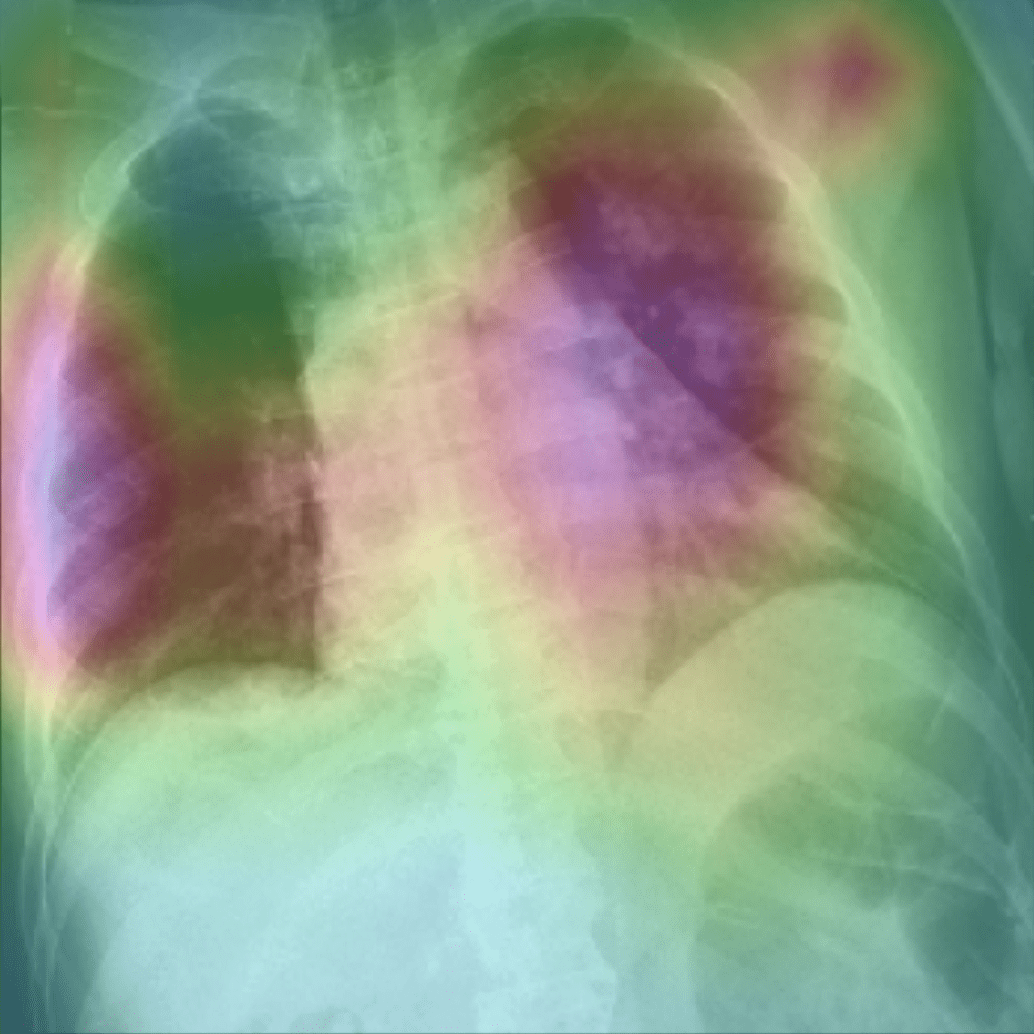

Appendix B More Grad-CAMs of the COVID-CXNet Model with Lung Segmentation Preprocessing

Refer to caption

Figure 21: Grad-CAMs from COVID-CXNet with lung segmentation module